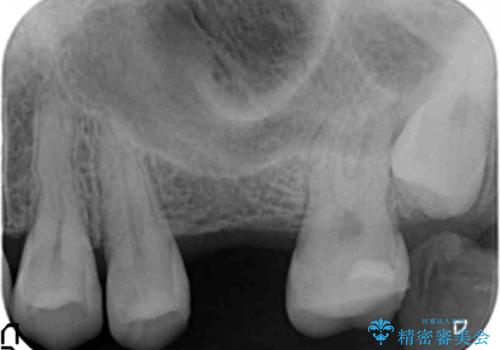

- 前歯のがたつきを主訴に来院。

奥歯も少なく、左上奥歯はブリッジにすることになりました。

左下の前歯を中に入れるスペースを確保する目的で左下の奥歯を後ろ移動させました。

また、左下の小臼歯の捻転はマウスピースで治りにくいため、

事前にワイヤーによる部分矯正を行い、矯正用ミニスクリューを植立しています。